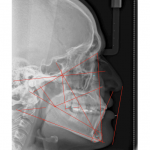

• A través de sencillas pero poderosas herramientas se pueden hacer trazados cefalométricos que permitan al médico observar, analizar y/o diagnosticar detalladamente y con mayor rapidez y confiabilidad.

- Ricketts